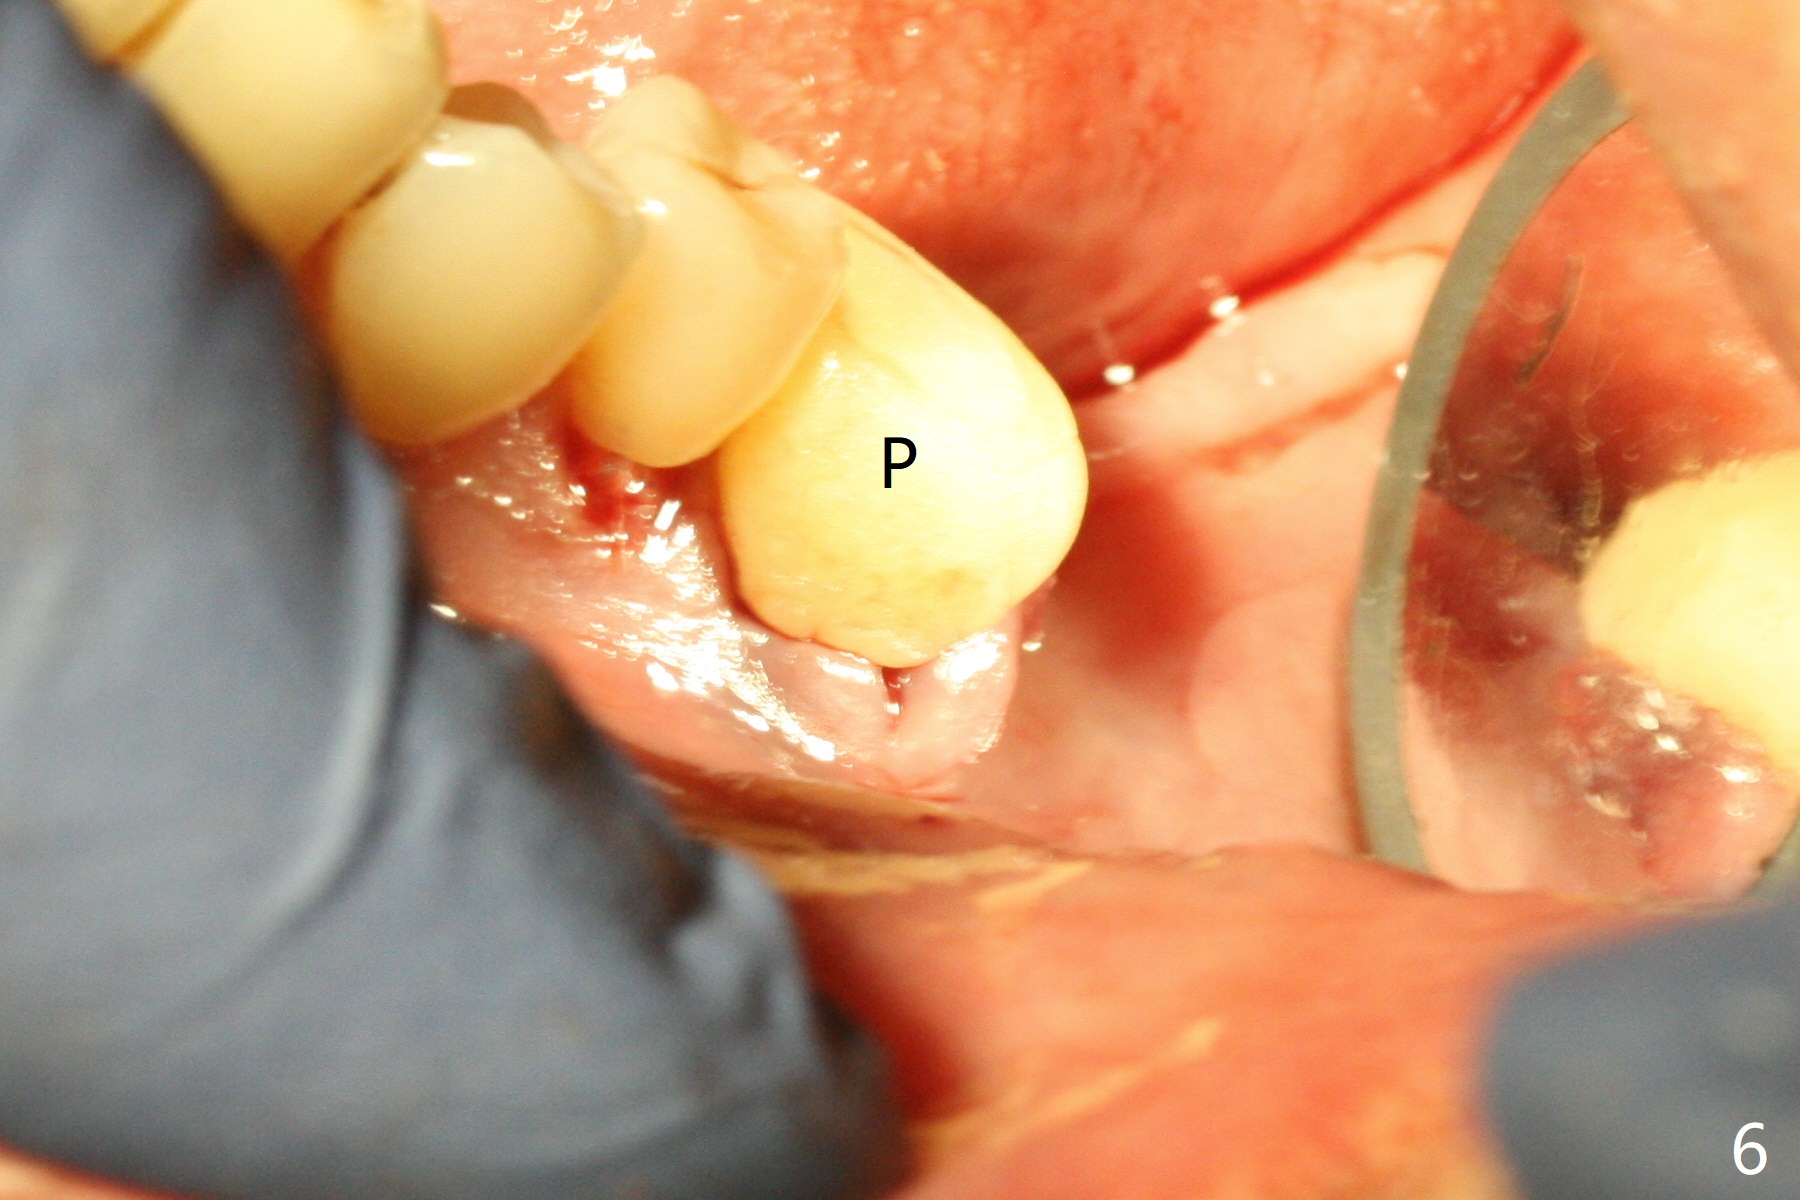

When the patient returns for #19 extraction (Fig.1), there is no 5x10 mm implant available. In fact the smaller one (4.5x10 mm) is able to achieve insertion torque >60 Ncm with more room for autogenous bone/allograft horizontally (Fig.2 *). After insertion of a definitive abutment (6.5x5.5(4) mm), more allograft is placed coronally (Fig.3 *). The gingiva that was between the mesial and distal roots before extraction (Fig.1 *) is transferred distal (Fig.4.5 *). An immediate provisional (Fig.6 P) is fabricated to close the socket opening, followed by periodontal dressing (data not shown). The latter is partially detached 2 weeks postop (Fig.7 D). When it is removed, some of possibly collagen plug is exposed distobuccally (Fig.8). When the plug is removed, some of the bone graft (Fig.9 *) is exposed distal to the provisional (P). New periodontal dressing is applied to keep the exposed graft in place. There is no apparent thread exposure 4 months postop (Fig.10). The abutment is loose 4 months post cementation, probably related to unfavorable crown/implant ratio; but when the abutment is retightened, there is a gap between it and the implant (Fig. 11 >). After relieving the proximal contact of the crown, the abutment is retightened one more time with the same gap (Fig.12 >). In fact the latter is present previously. A narrower abutment with longer cuff appears to be completely seated, probably avoiding contact with the regenerated crestal bone (Fig.13 *). If the new crown gets loose, bury a driver inside the abutment.